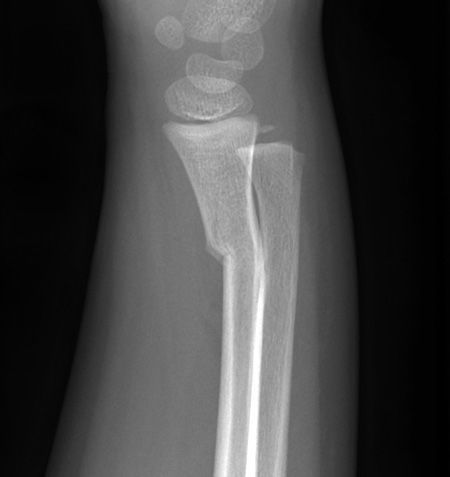

TRAUMA X-RAY 70: Child with injured forearm. What is the name given to this injury? Answer bit.ly/3idqJLF